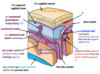

Name structures A-D

Name vessels A-F

Name vessels A-E

Name vessels A-E

Name vessels A and B

Name structures A-D

Name structures A-B

Name structures A-D